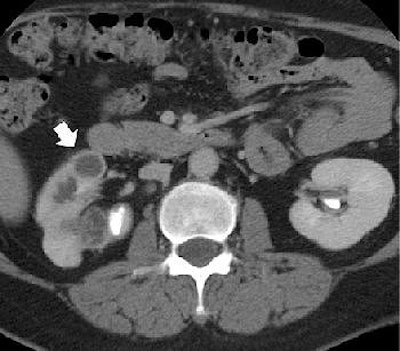

![]() |

| Image B. Magnified view from a contrast-enhanced nephrographic-phase CT scan, obtained caudad to image A, shows mural enhancement and thickening of the proximal ureter (arrow). Figures 2a, b, Gibson MS, Puckett ML, Shelly ME, "Renal Tuberculosis," (RadioGraphics 2004; 24: 251-256). |

With conventional radiography, renal calcifications are a common manifestation of tuberculosis occurring in 25% to 44% of patients. CT is useful in determining the extent of renal and extra renal spread of the disease. Coalesced cortical granulomas and parenchymal scarring is apparent at CT, while fibrotic structures of the renal pelvis and ureters may be seen on contrast-enhanced CT, suggesting tuberculous infection.